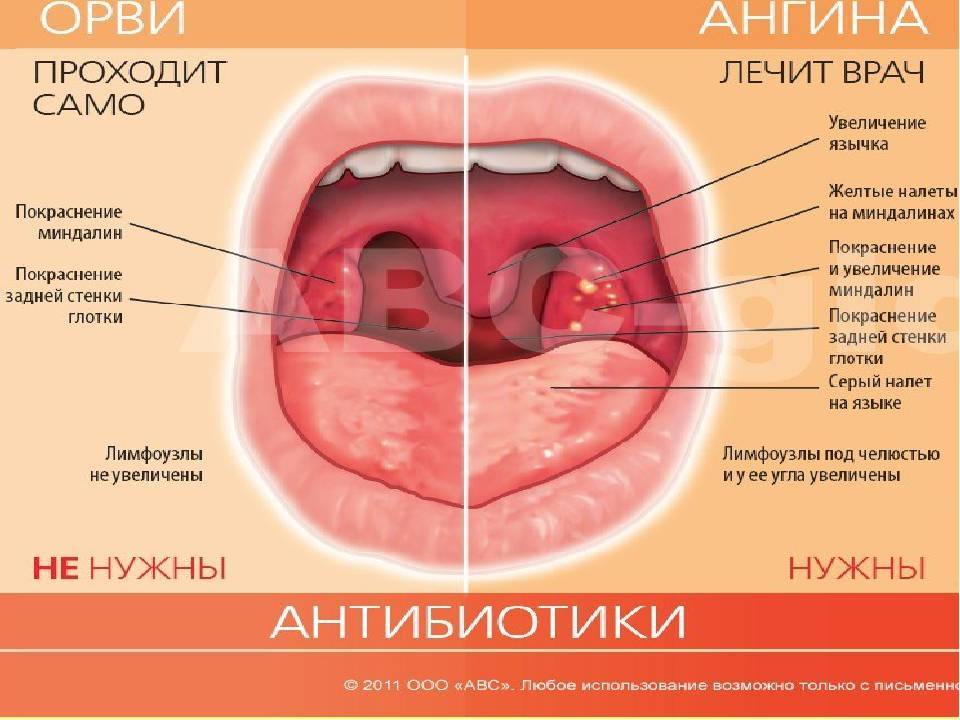

- Местное лечение болезни. Данный метод является обязательным условием терапии. Полоскания и орошения горла направлены на дезинфекцию полости и уменьшению симптоматики. К самым эффективным местным средствам относят: полоскания горла раствором Фурацилина, содовым и солевым раствором с йодом.; полоскания настоями лекарственных трав в виде ромашки, календулы, шалфея; орошение горла раствором морской соли; орошение горла лекарственными средствами в виде Мирамистина, Гексорала, Каметона; рассасывание противовоспалительных и антибактериальных таблеток в виде Граммидина, Стрепсилса, Лизобакта, Фарингосепта.

Клиническое течение при ангине у каждого ребенка может отличаться, учитывая тип заболевания:

- Катаральная, которая является наиболее распространенной и протекает легче, чем другие типы болезни. Проявляется поверхностным поражением миндалин с появлением небольших красных участков на слизистой оболочке. Симптоматика выражена не остро, при этом возможно незначительное повышение температуры до 37-38°С. Ребенку часто ставится такой диагноз при развитии заболеваний верхних дыхательных путей.

- Фолликулярная или гнойная. Отличается более острым течением, часто сопровождается высокой температурой – 38°С и выше. При подобной форме на миндалинах можно обнаружить небольшие белые или желтые гнойники не больше 2 мм. При гнойной ангине увеличиваются и болят при пальпации лимфоузлы на шее и затылочной части.

Классификация ангины

По степени воспаленности миндалин, ангина у детей может иметь несколько видов:

- катаральная. При осмотре зева видно, что небные дужки, миндалины увеличены и покрыты серозным белесоватым налетом;

- фолликулярная. Характерным признаком является наличие гнойных точек на миндалинах, размер которых может быть до трех миллиметров;

- лакунарная. Осмотр зева, открывает отекшие и сильно покрасневшие миндалины, покрытые налетом гноя, желтого цвета;